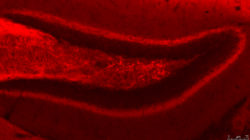

Ja sigui alcohol, tabac, cocaïna o cànnabis, les drogues creen una dependència de la que és difícil sortir-ne. Expliquem com funcionen les addiccions al cos i quina recerca s’està portant a terme al respecte.